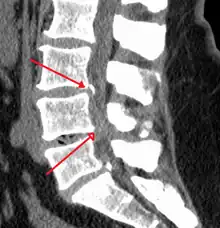

Stenoza spinală reprezintă îngustarea anormală a canalului spinal sau foramenului neural care duce la o presiune asupra măduvei spinării sau a rădăcinilor nervoase[3]. Simptomele pot include durere, senzație de amorțeală sau slăbiciune la nivelul brațelor sau picioarelor[4]. Simptomele se manifestă de obicei progresiv și se îmbunătățesc în timpul aplecării în față[4]. Simptome severe pot include pierderea controlului vezicii urinare, pierderea controlului intestinal sau disfuncții sexuale[4].

Cauzele acestei boli pot include osteoartrita, artrita reumatoidă, tumorile medulare, traumatismele, boala Paget a osului, scolioza, spondiloza și boala genetică numită acondroplazie[5]. Stenoza spinală fi clasificată în funcție de partea coloanei vertebrale afectate în stenoză cervicală, toracală și lombară[6]. Stenoza lombară este cea mai des întâlnită formă, urmată de stenoza cervicală[6]. Diagnosticul este în general bazat pe simptome și imagistică medicală[7].